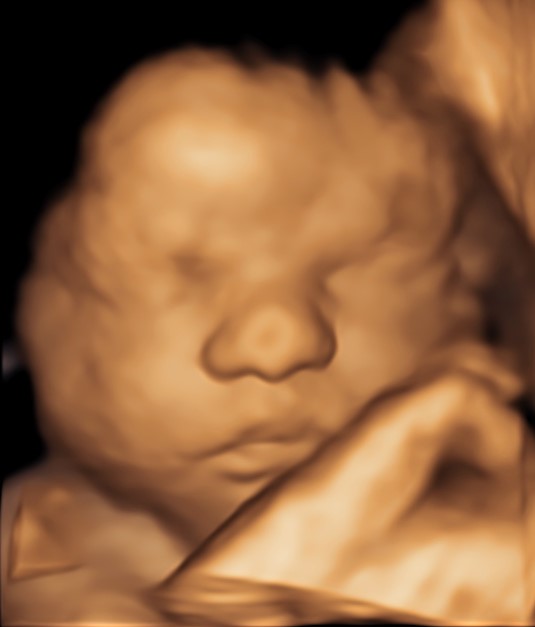

4D/5D/HD Ultrasound Gallery

Gallery